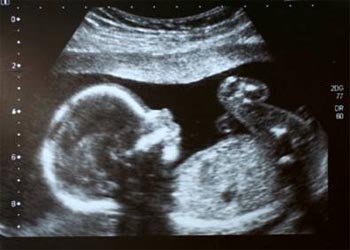

#3 Ultrasound Scanning

Year: 1956

Ultrasound is an oscillating sound pressure wave with a frequency greater than the upper limit of the human hearing range.Ultrasound is used in many different fields. Ultrasonic devices are used to detect objects and measure distances. Ultrasonic imaging (sonography) is used in both veterinary medicine and human medicine. In the nondestructive testing of products and structures, ultrasound is used to detect invisible flaws. Obstetrician Ian Donald and engineer Tom Brown developed the first prototype of medical ultrasonography in 1956 in Glasgow.